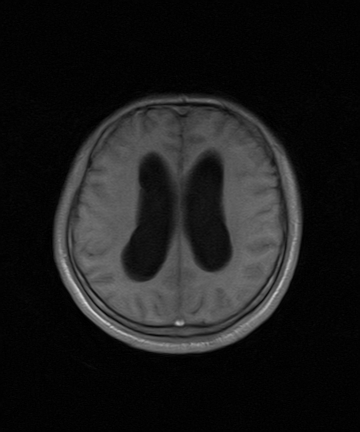

标题: MRI2064:少见病例。男性52,视力下降多年。 [打印本页]

标题: MRI2064:少见病例。男性52,视力下降多年。

四脑室区见混杂信号占位影,脑室系统扩张明显,临近结构显著受压称位,患者52岁,多考虑室管膜瘤可能性大

考虑第四脑室室管膜瘤并梗阻性脑积水;部分性空蝶鞍;左侧上颌窦粘膜下囊肿。